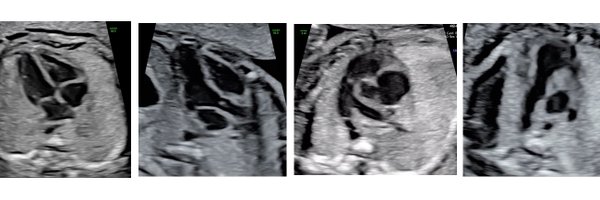

Key takeaways from PA/IVS: From the Fetus to the Adult Session at #ASE2025 🫀chaired by @shubhi_srivas 🔹 Fetal echo: TV annulus Z, TR, RV/TV growth, PV type, sinusoids, LV function guide prognosis 🔹 Postnatal: Echo + cath crucial for RV size, interatrial comm, RVDCC, RV

You're invited! FHS Monthly Webinar – March 13, 2025 Please join the Fetal Heart Society for our next free educational webinar, “Can You See Me Now? Optimizing Fetal Cardiac Imaging,” on Thursday, March 13, 2025, at 8:30 PM ET. Register now! https://t.co/PwsmqjkpCH